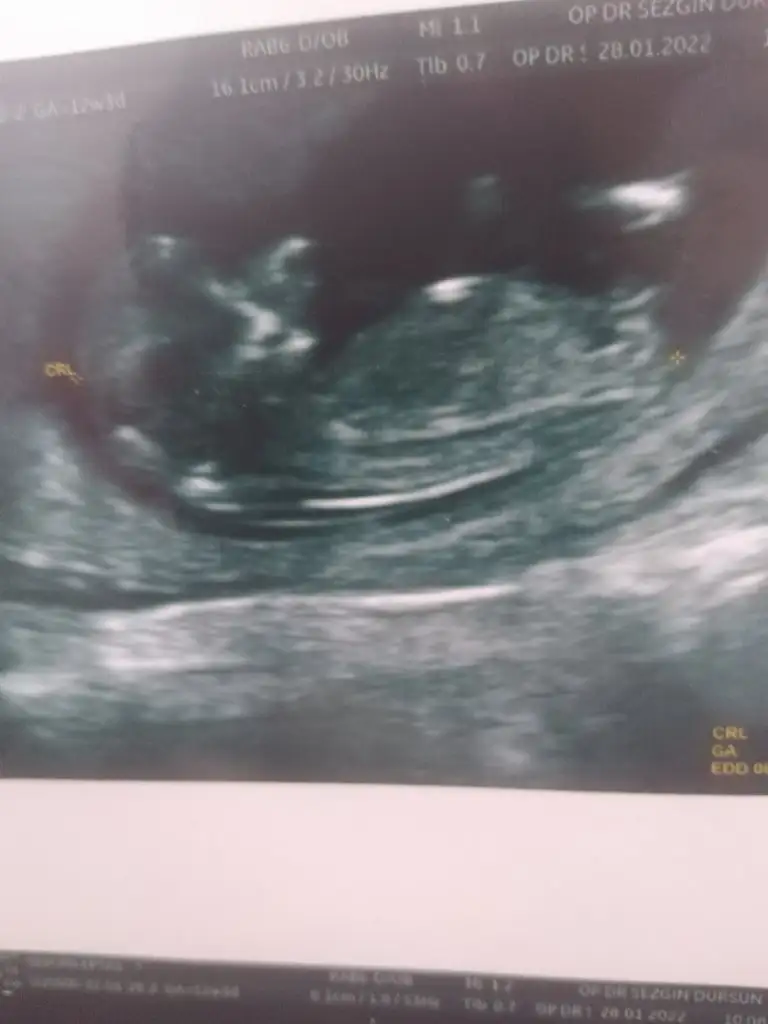

IMG_20220129_134107.webp

12+3 karından çekildi